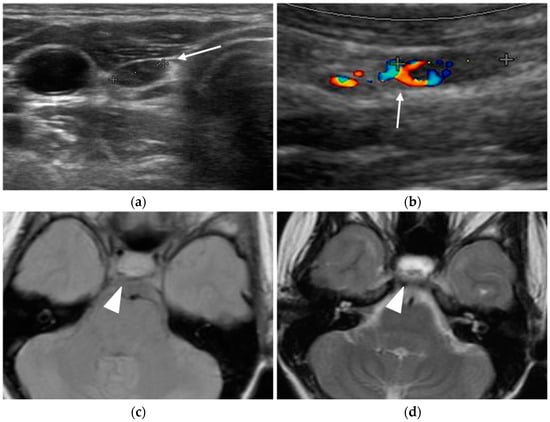

The most common neoplasms associated with MEN-1 syndrome are parathyroid tumors, pancreaticoduodenal neuroendocrine tumors (NETs), and anterior pituitary tumors (Figure 1).

Figure 1.

Young female MEN-1 patient, aged 19 at initial diagnosis. Ultrasound revealed a parathyroid adenoma (arrow in a,b) and MRI highlighted a pituitary macroadenoma (arrowhead in c–e) and a pancreatic NET (arrow in f).